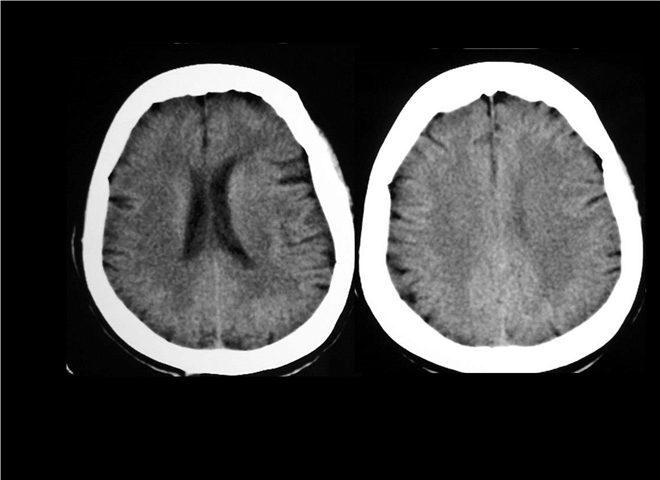

13_CT增强扫描